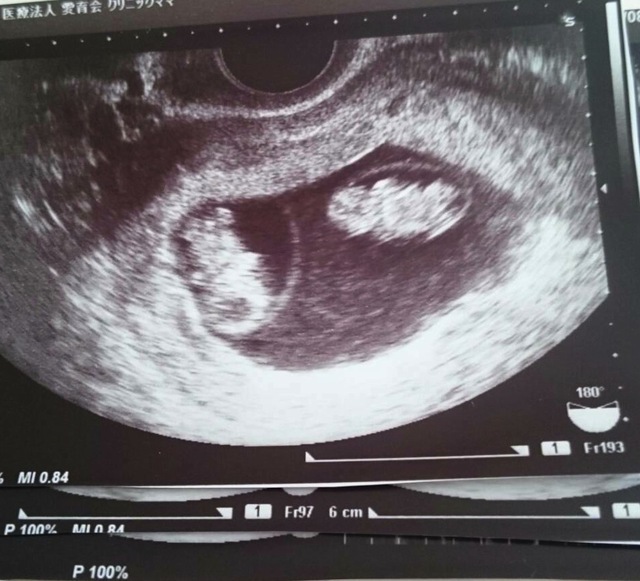

9週0日(9w0d・性別不明・双子)|みーやま さん(27歳)

エコー写真撮影時のエピソード:

なかなか授からず、3年目にして授かり毎回検診でちゃんと育っているか不安でした。この9wの時、双子が発覚!!驚きとうれしさと不安にもなりました。

けど、旦那も親も喜んでくれて、今まで不妊治療を頑張ってきて本当に良かったと思いました。つわりも妊娠後期も体調がよくなく、管理入院になりましたが、無事元気に生まれてくれて、今本当に幸せです。